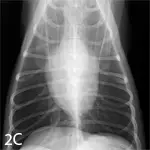

With increased opacity, many diseases will present with a mixed pulmonary pattern, so the dominant pattern should be identified to formulate an appropriate differential list (Figure 5). More important, the anatomic distribution will drive the prioritization process for differentials. For example, cranioventral typically equates with infectious disease (bacterial pneumonia), whereas caudodorsal typically equates with edema (cardiogenic or noncardiogenic).

Lateral radiographs from various dogs with increased lung opacity; ventral alveolar pulmonary pattern (A), generalized bronchial pulmonary pattern (B), vascular pulmonary pattern in a dog with a left-to-right shunting patent ductus arteriosus (C), structured interstitial pulmonary pattern in a dog with pulmonary nodules secondary to renal carcinoma metastatic disease (D), and an unstructured interstitial pulmonary pattern (E)